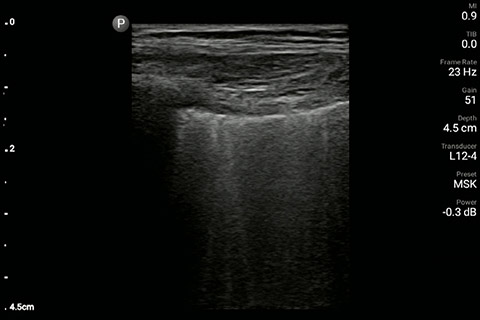

The patient had reduced LV systolic function without new or severe valvular pathology, a dilated, non-collapsing IVC, and diffuse B lines (left greater than right) on lung ultrasound imaging.

M-mode demonstrating lung sliding